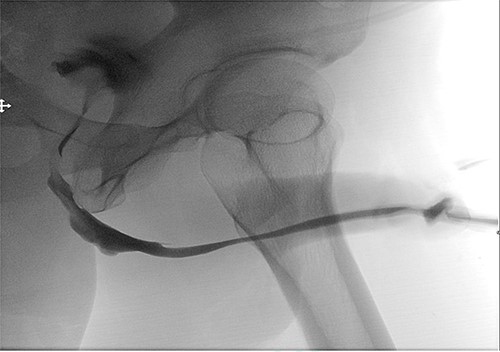

A retrograde urethrogram was performed after 4 weeks which revealed no leakage, and a patent urethra with a wide anastomotic site at the bulbar urethra Fig. 5. Urethroscopy was also performed, and it confirmed an easy passage with no stricture recurrence. Therefore, the urethral catheter was removed. The uroflowmetry showed an excellent Q max 29 ml/s and voided 378 ml with minimal post voiding residual 30 ml/s. The patient was happy with the results.

Postoperative retrograde urethrogram revealing no leakage, and a patent urethra with a wide anastomotic site at the bulbar urethra.